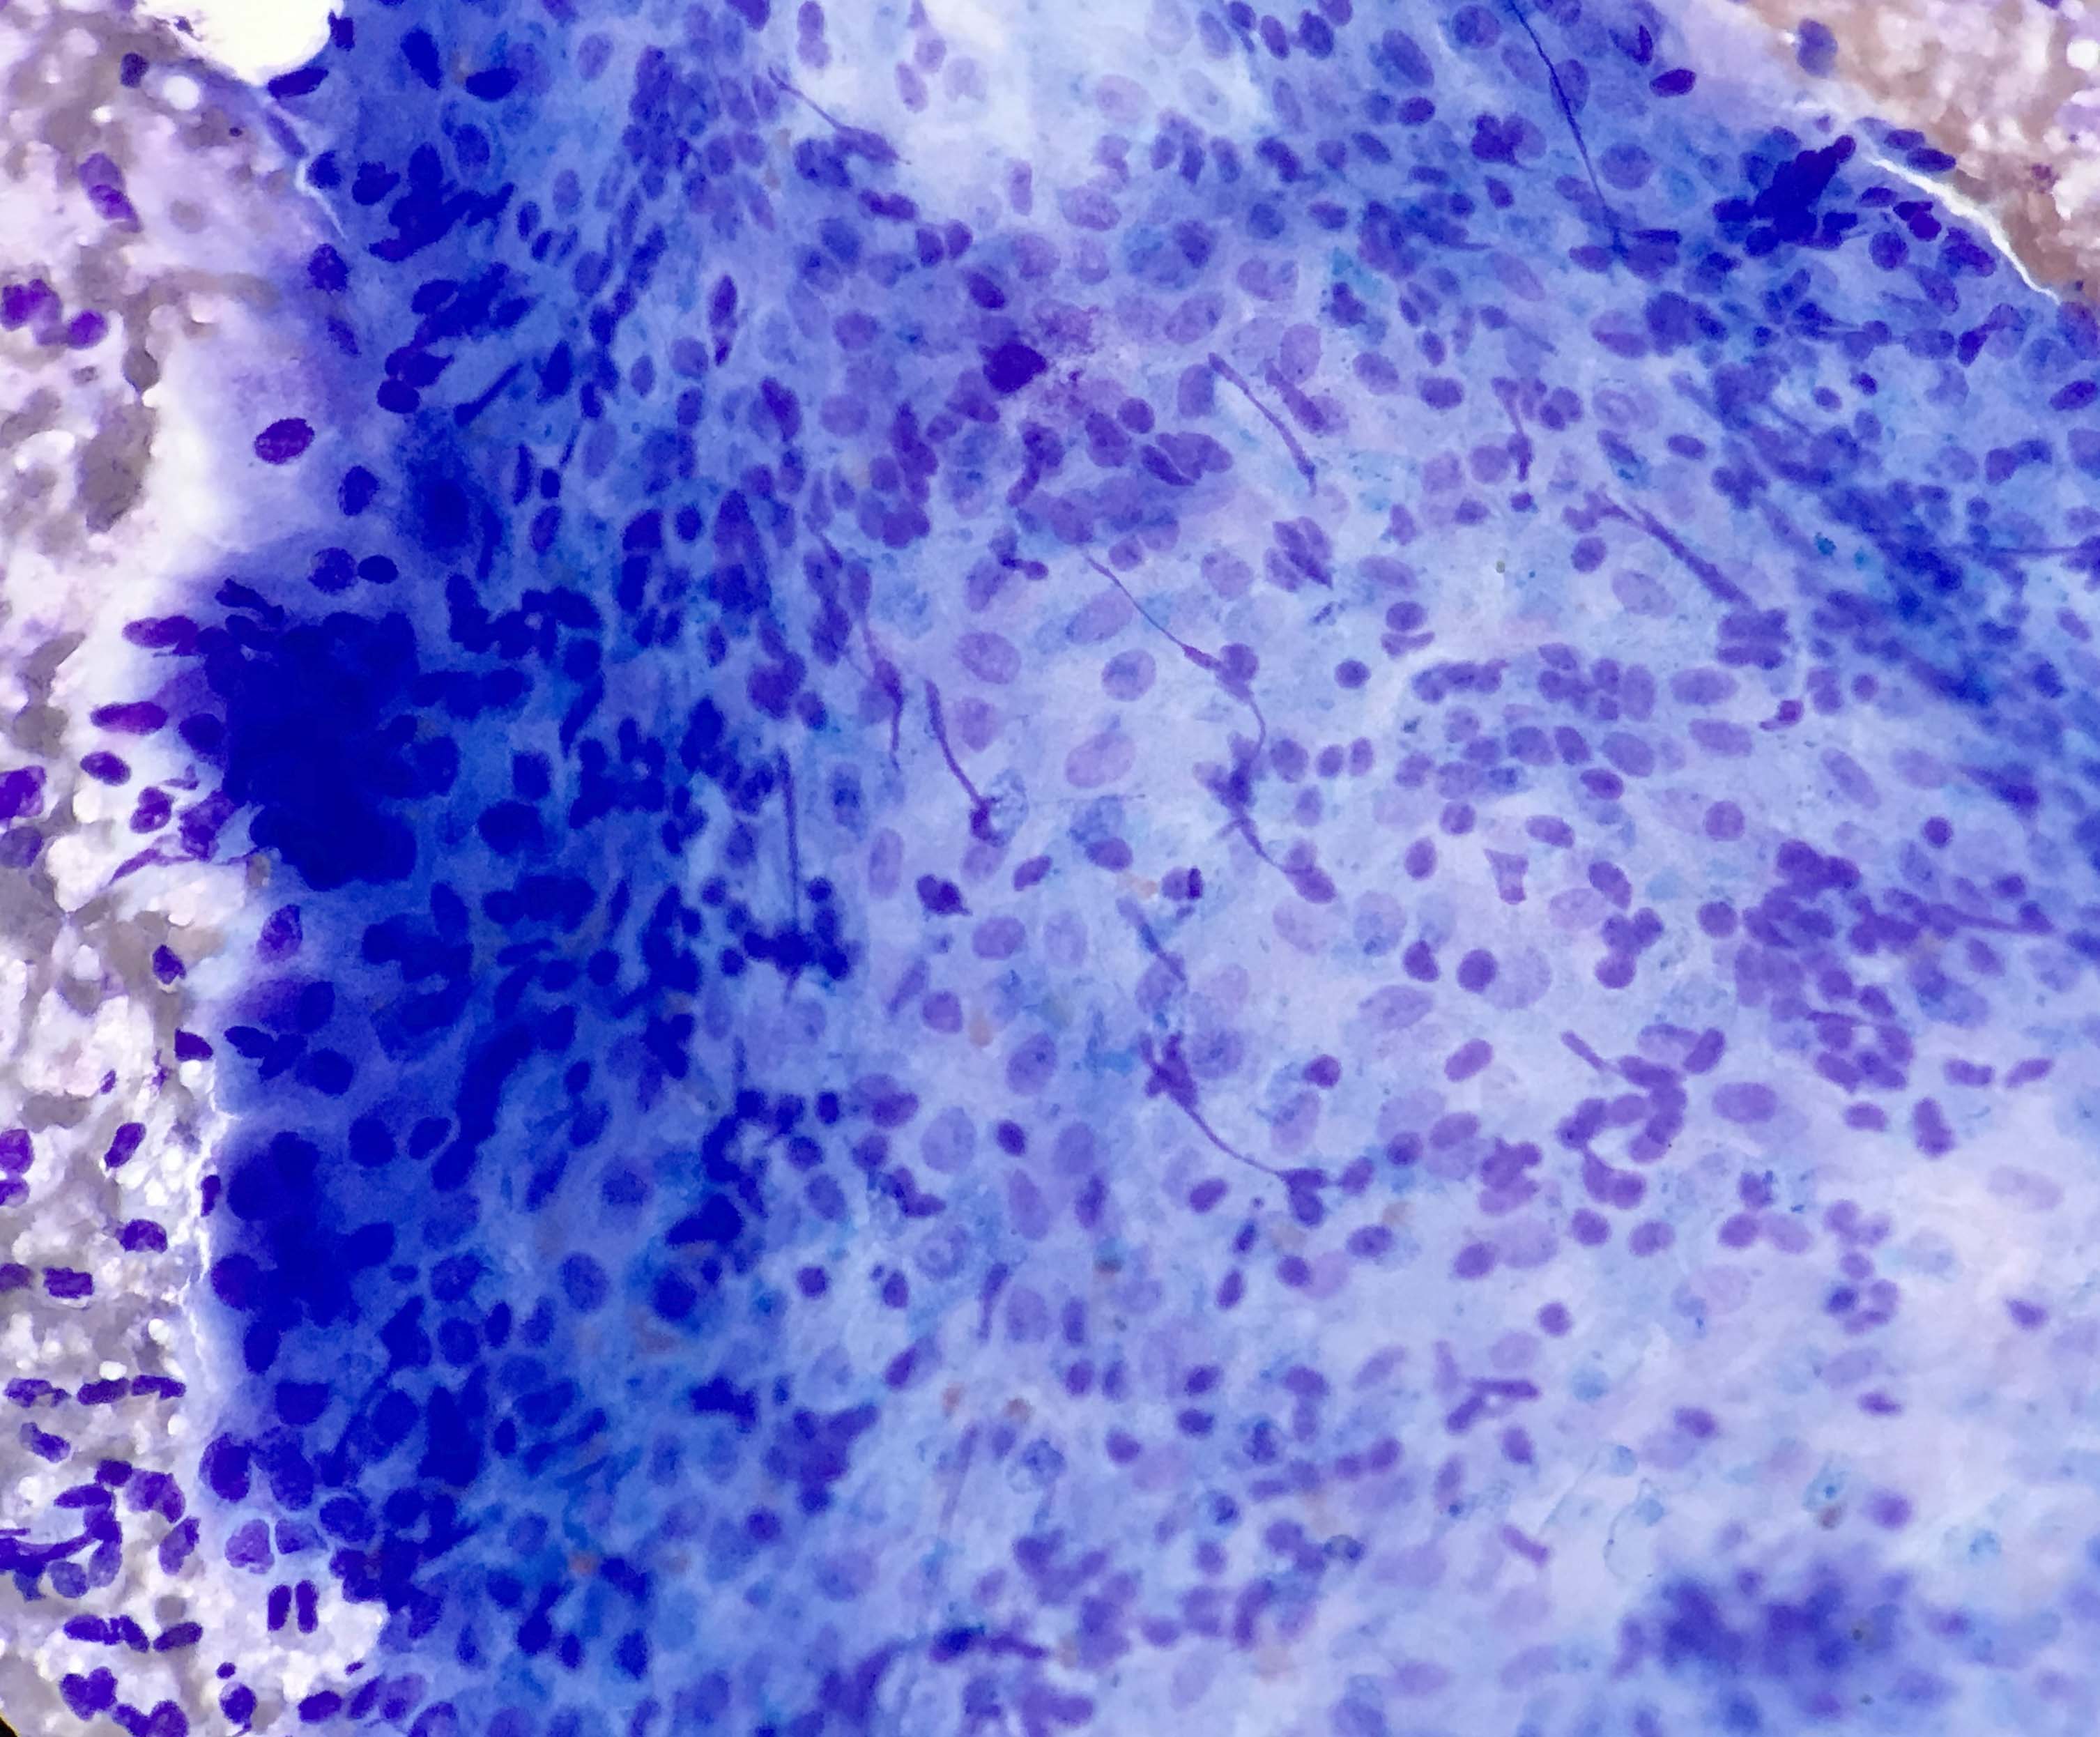

Contributed by Kelly Magliocca, D.D.S., M.P.H. and Anne C. McLean-Holden, D.M.D., M.S.

Cytology description

- Compact and cohesive cell clusters with areas of short branching of tumor cells along the periphery (Diagn Cytopathol 2013;41:206)

- Oval to round basaloid cells with high nuclear to cytoplasmic ratios, fine powdery chromatin, nucleoli with small peripheral nucleoli to inconspicuous nucleoli

- Squamous cells centrally with more abundant cytoplasm (particularly in acanthomatous variant)

- Possible limitations to FNA

- Inadequate sampling due to extensive cyst formation within the tumor

- Inability to distinguish ameloblastoma with macrocystic degeneration from ameloblastoma, unicystic type

- Inability to distinguish ameloblastoma from metastatic ameloblastoma without prior knowledge of metastatic disease

- Inability to distinguish ameloblastoma from other benign odontogenic tumors that are managed with curettage (e.g. adenomatoid odontogenic tumor, ameloblastic fibroma) (Diagn Cytopathol 2013;41:206)